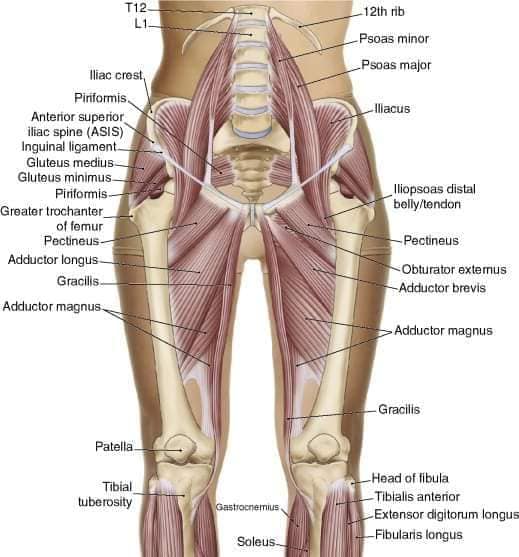

Скелетно-м'язова система людини (синоніми: Опорно-рухова система, опорно-руховий апарат, кістково-м'язова система, локомоторна система) — комплекс структур який утворює каркас, надає форму організму, дає йому опору та забезпечує захист внутрішніх органів і можливість пересування у просторі. Це функціональна сукупність кісток скелета, їх з'єднань (суглобів і сінартрозів), і соматичної мускулатури з допоміжними пристосуваннями, які здійснюють за допомогою нервової регуляції локомоції, підтримання пози, міміки та інших рухових діях, поряд з іншими системами органів утворює людське тіло.

Це саморушний механізм, який складається з 400 м'язів, 206 кісток і декількох сотень сухожиль. Більшість кісток скелету з'єднане рухомо за допомогою суглобів. Одним кінцем м'яз прикріплюється до однієї кістки, утворюючи суглоб, іншим кінцем — до іншої кістки. В англомовній літературі застосовують близькі за значенням терміни: англ. musculoskeletal system (скелетно-м'язова система) та англ. locomotor system (локомоторна система).

М'язова система людини є однією з основних систем організму, що відповідає за рухи, підтримання пози та стабільність. Вона складається з понад 600 м'язів, які можна класифікувати на скелетні, гладкі та серцеві м'язи. Скелетні м'язи, які є об'єктом нашого детального розгляду, дозволяють контролювати навколишній світ і виконувати різноманітні рухи. Особливу увагу в нашій статті буде приділено шейним і спинним м'язам, оскільки ці групи м'язів мають критичне значення для підтримання правильного постава та функціонування хребта.

Скелетні м'язи з'єднані з кістками за допомогою сухожиль і відповідають за більшість волевих рухів. Вони поділяються на:

- Швидкі м'язи - призначені для швидких і потужних рухів.

- Повільні м'язи - забезпечують стійкі і довготривалі рухи.

Скелетні м'язи мають поперечну смугасту структуру, що забезпечує їхню здатність до швидкого і ефективного скорочення.